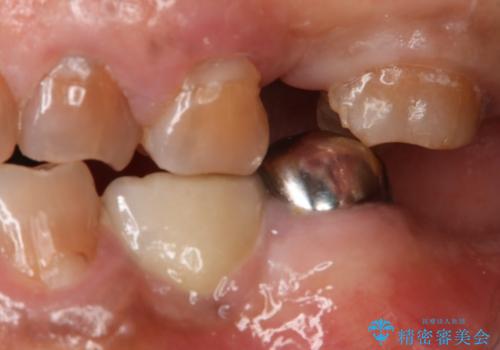

奥歯のスペースを埋めたい フルジルコニアブリッジ

- 左上臼歯部に保険のブリッジを入れていたがすぐに取れてしまったので自費治療でのやり変えを希望された患者様です。

インプラントとブリッジを提案しましたが時間をかけたくないとのことだったので、ブリッジでの治療を選択しました。